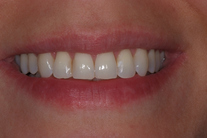

32-årig kvinna som tycker att hon bara visar sina framtänder. En utjämning och vidgning av tandbågen med 8 månaders genomskinliga Invisalignskenor, gav henne ett fint leende.